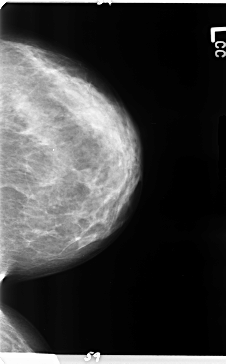

B_3157_1.LEFT_CC

LEFT_CC LINES 4720 PIXELS_PER_LINE 2928 BITS_PER_PIXEL 12 RESOLUTION 50 NON_OVERLAY